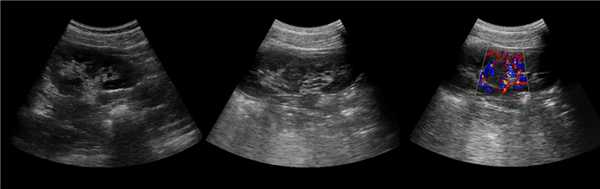

Рисунок. На УЗИ почечное ложе слева пустое (1). Обе почки расположены справа, срастаются полюсами (2, 3). Заключение: Аномалия взаиморасположения почек — I-образная удвоенная правая почка.

Рисунок. На УЗИ в малом тазу (мочевой пузырь — акустическое окно) определяются почки связанные узким перешейком (1, 3); дифференцировка паренхимы сохранена, кровоток прослеживается до капсулы (2, 3). Заключение: Аномалия взаиморасположения почек — сращение нижних полюсов тазово-дистопированных почек.